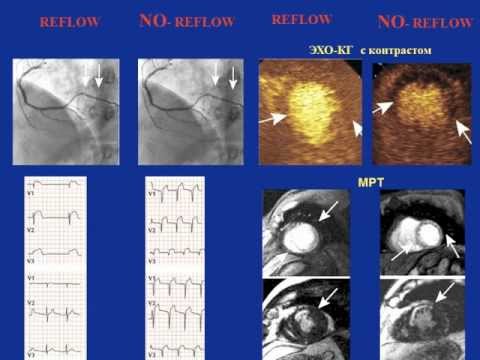

Жизнеспособный миокард (Школа кардиолога 2013)